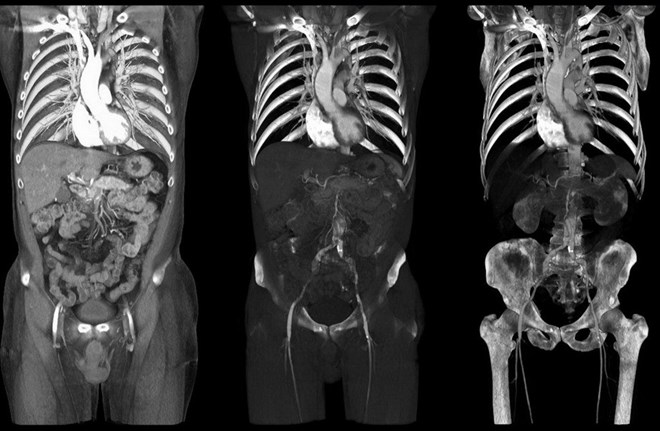

Một bác sỹ phẫu thuật tại một bệnh viện ở Massachusetts (Mỹ) đã cắt bỏ nhầm một quả thận của một bệnh nhân trùng tên với bệnh nhân có khối u.

Tờ Boston Globe cho biết bác sỹ này đã tiến hành chụp CT trước khi phẫu thuật, kết quả cho thấy có khối u trên thận. Tuy nhiên, kết quả chụp này là của một bệnh nhân khác.